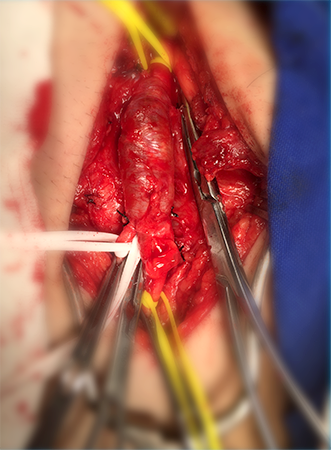

Endarterectomia de Carótidas

A deposição de colesterol e cálcio na parede das artérias carótidas pode levar ao Acidente Vascular Cerebral Isquêmico, que é a terceira causa mais importante de morte por doença na população. A partir de um determinado grau de estreitamento do vaso, está indicada a correção, seja através de angioplastia com colocação de stent, ou da remoção completa da placa de ateroma pela cirurgia de Endarterectomia. Apesar da Angioplastia com stent representar um avanço no tratamento desta doença, a cirurgia continua sendo a principal forma de correção para a maioria dos pacientes. Feita com anestesia geral, através de uma incisão no pescoço, o cirurgião abre a artéria doente, e remove toda a placa que provoca o estreitamento. Normalmente são necessários dois dias de internação hospitalar e o paciente estará apto a retomar suas atividades diárias imediatamente.